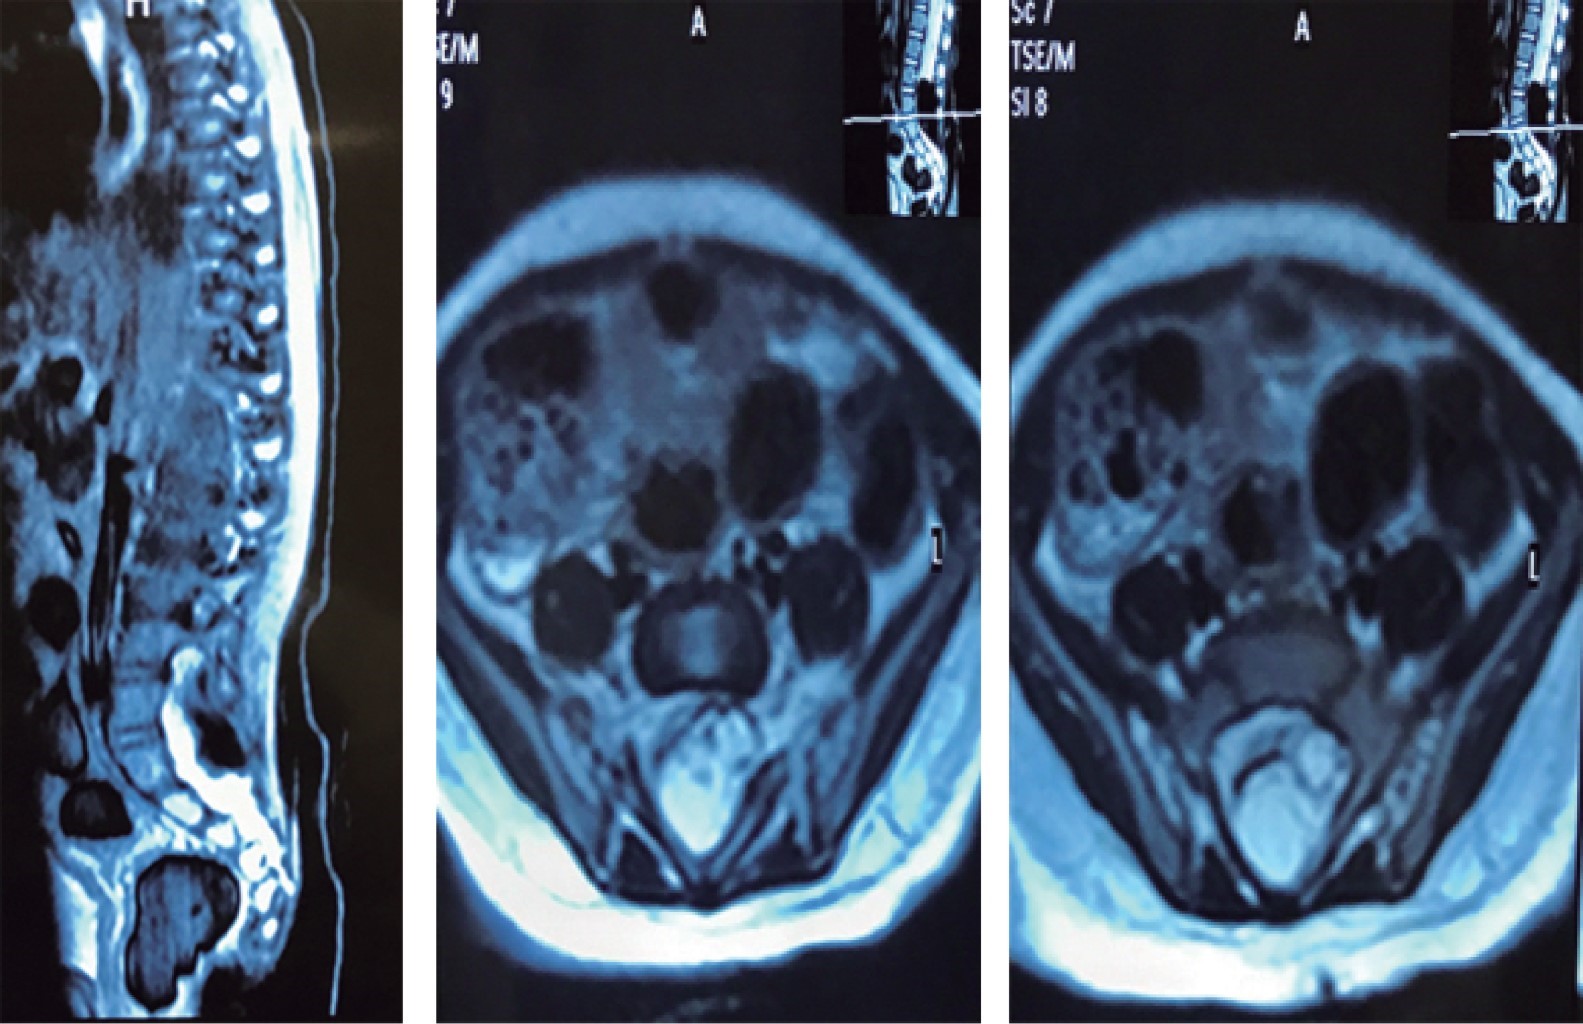

La lesión se caracterizaba por una neoformación subcutánea blanda al tacto, no fija a planos profundos y mal definida al tacto en cuyo centro se observaron unas placas angiomatosas circulares de límites regulares de fondo blanco-rojizo, asintomáticas (Figura 1). Por la topografía y características morfológicas se sospechó que se trataba de un defecto congénito de la columna vertebral, probablemente un lipoma subdural. Por tal motivo, se solicitó la opinión del neurólogo quien ordenó una resonancia magnética en la que se demostró la anomalía ya mencionada; el reporte de imagen corrobora un proceso ocupativo intradural de L4 a S1 compatible con lipomeningocele sumado y entremezclado con agregados vasculares mal definidos (Figura 2).